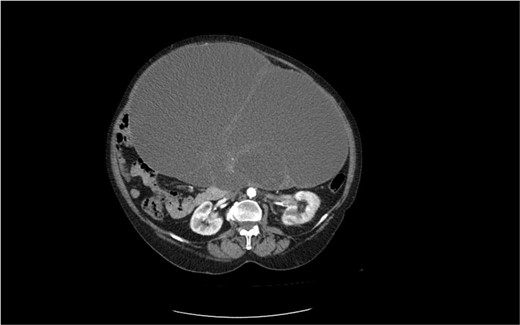

The second case is of a 62-year-old woman, admitted to a surgery clinic with abdominal distention, difficult defecation, and ultrasound data of a large tumor in the abdomen. CT describes a large tumor formation, reaching ventrally to the anterior abdominal wall, measuring 317/202/272 mm/d with a predominantly cystic structure (Fig. 3). The finding has a homogeneous content and multiple intralesional septa with a mass effect in relation to small intestine, main abdominal vessels, compress and dislocates the transvers colon and stomach. Operative treatment followed with laparotomy and evacuation of about 8 l of serous fluid from the cystic formation described on CT. Given the concerns about the presence of malignancy, a hysterectomy with adnexectomy and appendectomy was performed. Histopathologically, a multilocular mucinous cystadenoma of the left ovary was proven. The uterus has cystic endometrium and myometrium with intramural leiomyomas and adenomyosis, and the appendix with fibrinous-purulent periappendicitis. The patient recovered and was discharged on the seventh postoperative day without complications.